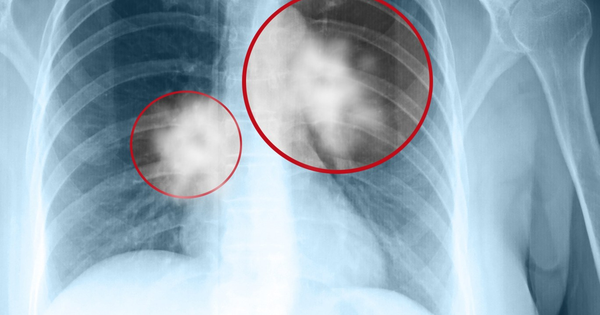

Theo thông tin từ bệnh viện, người vợ, một phụ nữ khoảng 60 tuổi, phát hiện khối u phổi kích thước 3cm khi đi chụp X-quang trong một lần khám sức khỏe tổng quát. Bà cho biết đã vô cùng bàng hoàng. Chồng bà đã qua đời vài năm trước vì ung thư phổi giai đoạn cuối, khi được phát hiện thì dịch phổi đã đầy, chỉ còn sống được một thời gian rất ngắn.